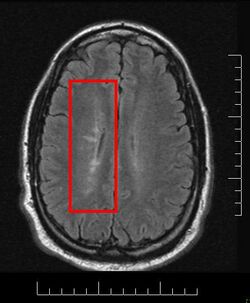

Dawson's Fingers appearing on an MRI scan

Multiple sclerosis is considered a disease of the white matter because normally lesions appear in this area, but it is also possible to find some of them in the grey matter.[30]

Due to the distribution of the lesions, since 1916 they are also known as Dawson's fingers.[40] They appear around the brain blood vessels.